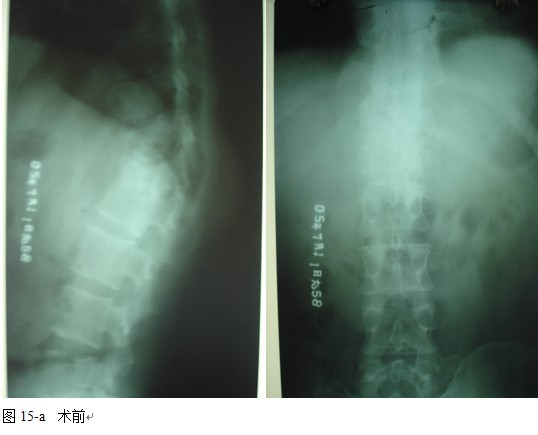

本组46例中男28 例,女18 例。年龄17~67岁,病程6 个月~7年,平均11.3 个月。本组患者均为 L1~S1腰段结核。病灶累及2 个椎体31例(L1-2 6例, L2-3 8例,L3-4 10例,L4-5 5例,L5-S1 2例),3 个或3 个以上椎体15例。合并腰大肌脓肿23列,所有患者均有腰背部疼痛,活动受限,双下肢感觉麻木19例,会阴部感觉减退12例,双下肢肌力减弱12例,腱反射减弱12例,术前后凸角(Cobb 角) <30°者12例, 30°~60°者28 例, >60°者6 例,Cobb角平均32.3°4例患者是二次手术。术前均行X线片、CT或者MRI检查。术后病理检查确诊为脊柱结核。

图11-a术前